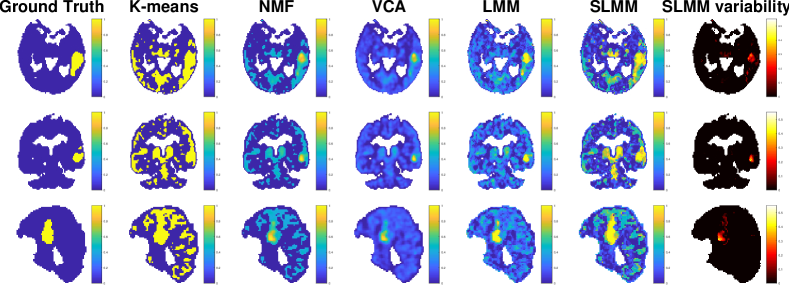

The algorithms have been applied to different realizations of the noise to get reliable performance measures. Table II presents the NMSE averaged over these realizations for all algorithms and variables of interest while Table III presents their corresponding variances. The factor proportion maps recovered by the compared algorithms are shown in Fig. 4. Each row corresponds to a specific factor: SBF, white matter factor, non-specific gray matter factor, blood factor (from top to bottom, respectively). The six columns contain the factor proportion maps of the ground truth, and those estimated by K-means, NMF, VCA, LMM and the proposed SLMM (from left to right, respectively). A visual comparison suggests that the factor proportion maps obtained with LMM and SLMM are more consistent with the expected localization of each factor in the brain than VCA. Meanwhile, they are less noisy than the maps obtained by NMF. The estimated LMM and SLMM proportions maps are closer to the ground truth than both of them, particularly in the region affected by specific binding, as quantitatively shown in Table II. It can also be observed that the factor proportion maps obtained with the proposed SLMM approach present a higher contrast compared to LMM and other approaches, especially in the high-uptake region.

The maps of SLMM are also sharper compared to LMM. Additionally, it is also possible to see that NMF results for white matter are sharper but also more noisy than both LMM and SLMM approaches. However, for the specific gray matter, both LMM and SLMM approaches show sharper estimated factor proportion maps. Note that the sharpness of the factor proportions is not necessarily a good criterion of comparison. Indeed, factor analysis-based methods do expect to recover smooth maps that take into account the spilling part of partial volume effect, which is not considered within deconvolution. The aim of unmixing is not hard-clustering or classification.

Taking into account the SBF variability allows the estimation of to be improved up to . Fig. 6 compares the actual variability factor proportions and those estimated by the proposed SLMM. This figure shows that the estimated non-zeros coefficients are correctly localized in the subregions characterized by some SBF variability. These non-zero values seem to be affected by some estimation inaccuracies, mainly due to the deconvolution. However, the estimation error still stays close to .